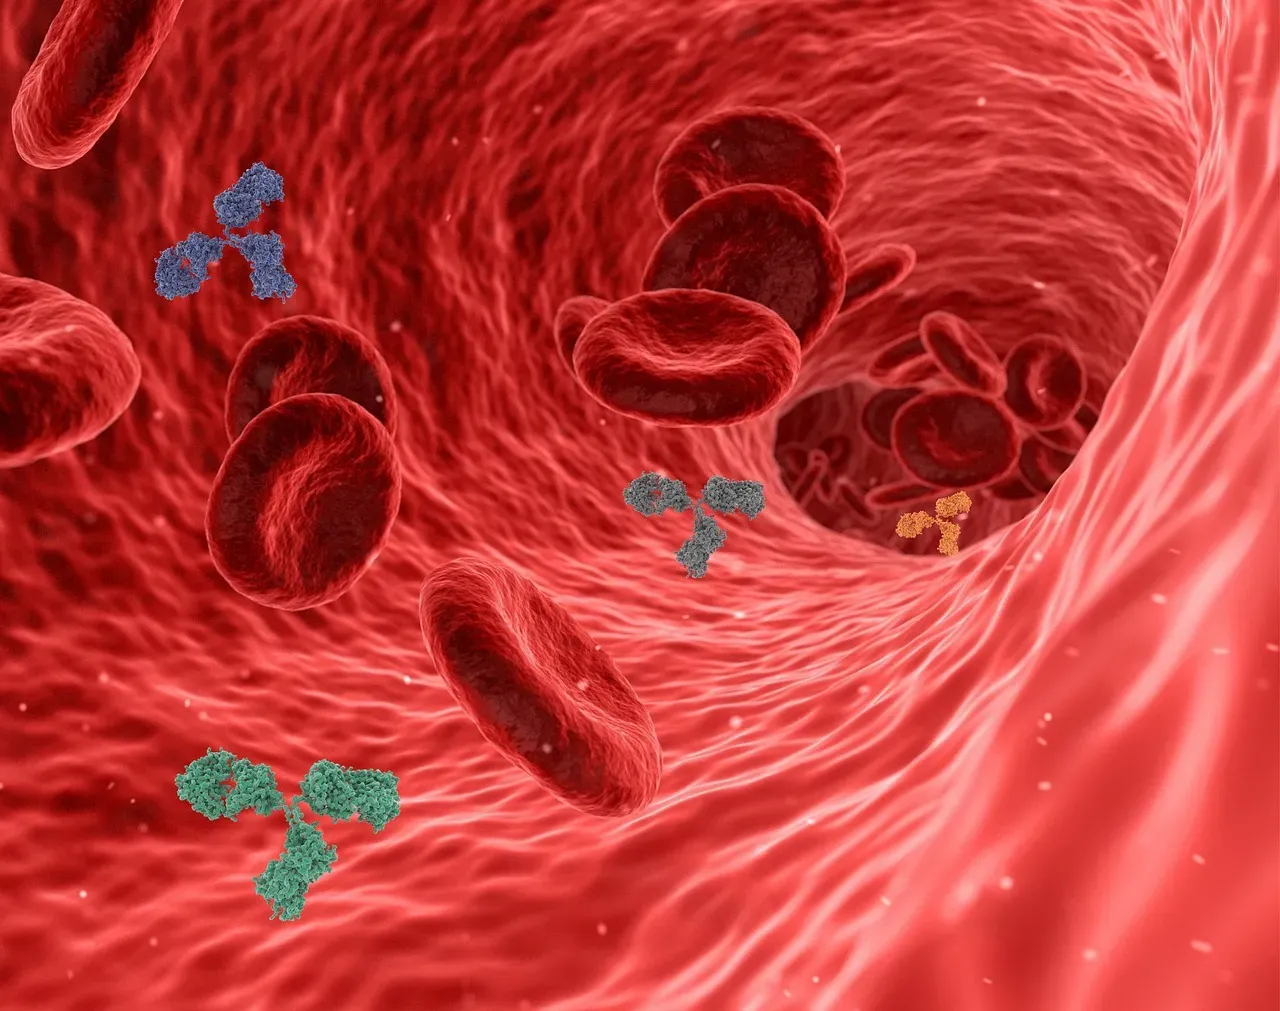

The Immune System’s “Memory” And Autoimmunity Paradox

Your immune system remembers past infections for years, sometimes for life, launching faster defenses if the same invader shows up again. That memory is the basis of vaccines and one of the great triumphs of biology. But the same system that can recognize a virus years later can also, for reasons we don’t fully understand, turn on your own tissues instead and cause autoimmune diseases like type 1 diabetes or multiple sclerosis.

Scientists have uncovered a lot about immune cells, antibodies, and inflammatory pathways, yet the line between healthy defense and self-destruction remains blurry. Why does one person’s immune system tolerate their own cells, while another’s mislabels them as enemies? Environmental triggers, gut microbes, infections, genetics – they’re all suspects, but there’s no single master explanation. It’s as if the body’s security guards not only learn faces but can occasionally become paranoid, and we still don’t know exactly what pushes them over that edge.